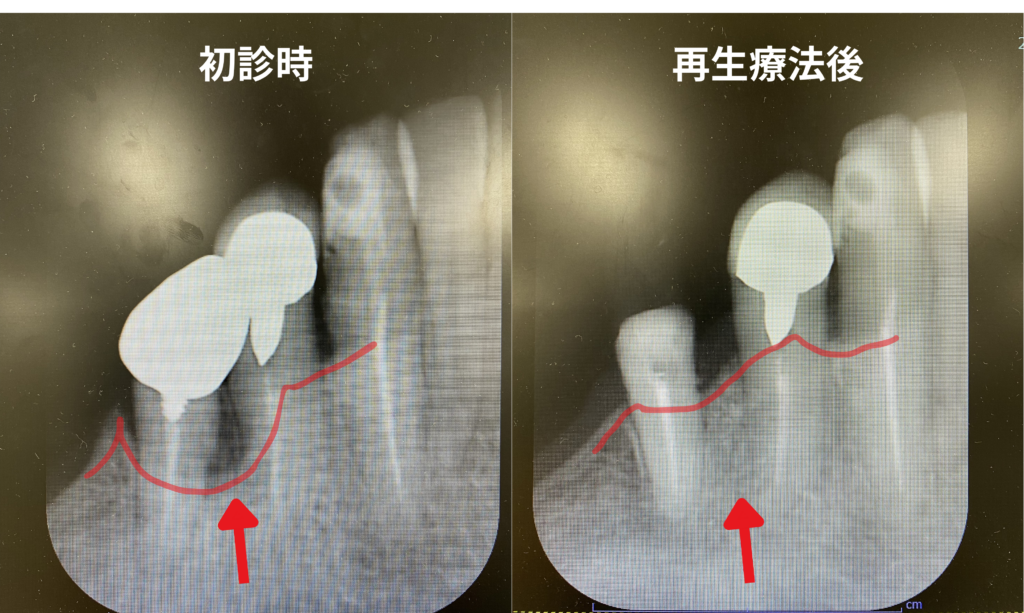

1璧性骨欠損に対し、「エムドゲイン+骨補填剤 +メンブレン(コラーゲン膜)」を併用した歯周組織再生療法を行い、歯槽骨の再生が獲得された1症例

従来の治療は「これ以上、骨が溶けるのを防ぐ」ことでした。再生療法はその一歩先、「失われた骨をを再生すこと」を目指します。

再生療法とは、特殊な薬剤や材料を用いて、体が持つ再生能力を最大限に引き出す治療です。